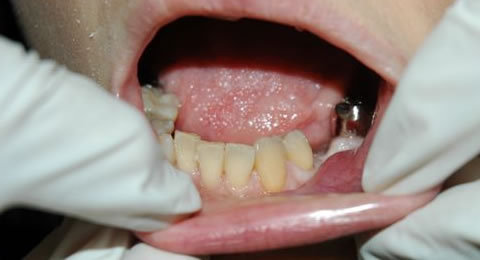

入れ歯をずっと使用していたそうで、入れ歯の違和感でお見えになられました。

この症例は入れ歯、インプラント、ブリッジの治療が選択肢になりますが、ご本人の希望によりブリッジ治療で通院されることになりました。

5本のセラミッククラウンで治療しました。

※費用内訳(税込):セラミッククラウン5本 ¥632,500、仮歯5本 ¥55,000